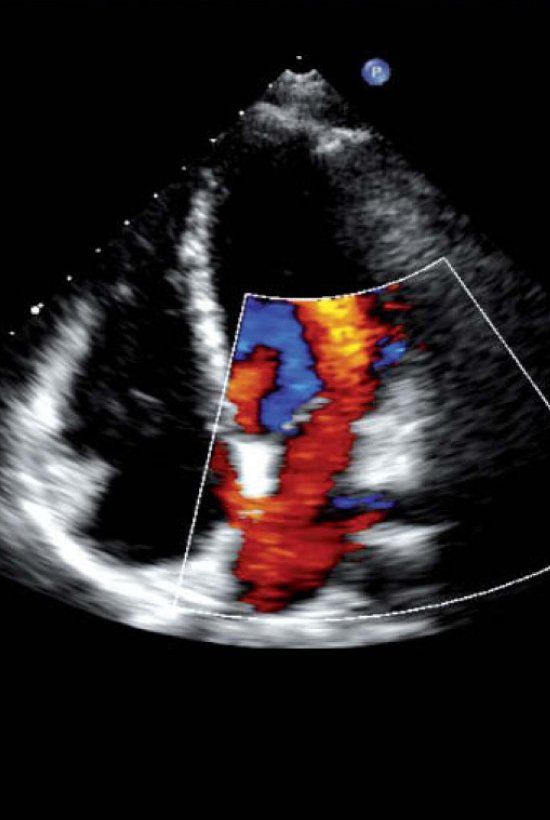

Eco Doppler Cardíaco

Estudios con tecnología moderna